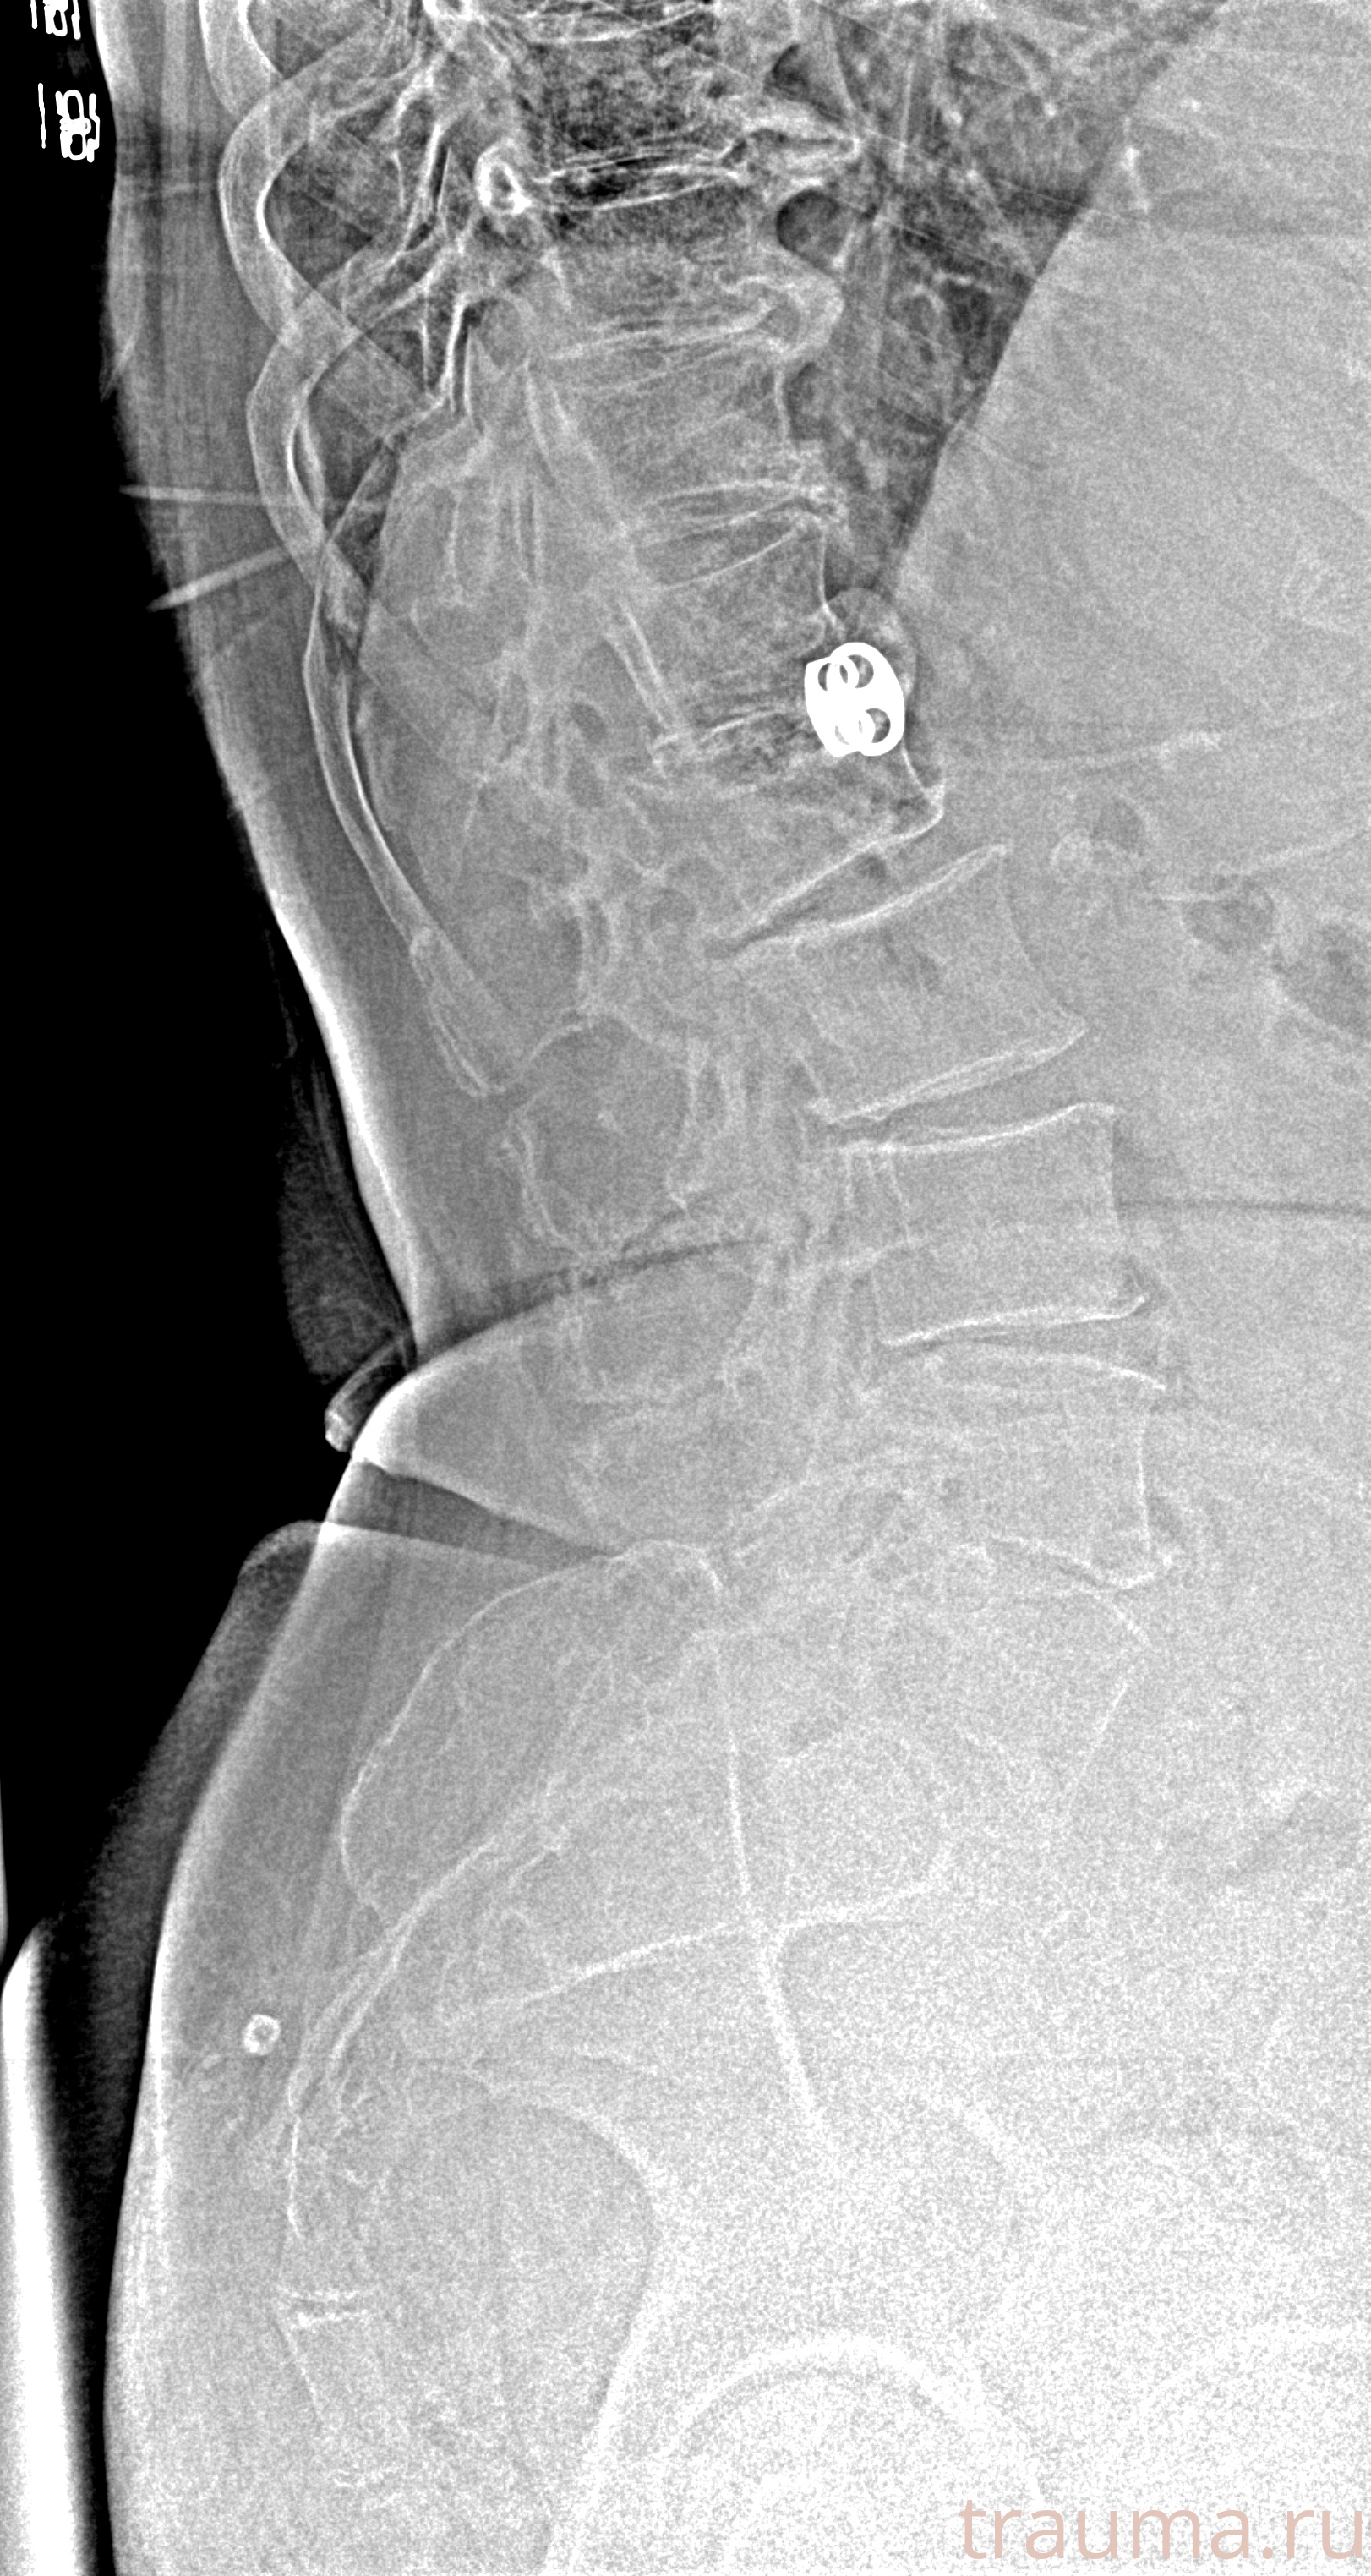

Рентгенограммы

Рентген на дому: по вашему адресу приезжает врач-рентгенолог, травматолог-ортопед с мобильным рентгеновским аппаратом, проводит диагностику травмы или заболевания, делает необходимые рентгенограммы, дает рекомендации по дальнейшему лечению. Получить качественные снимки в домашних условиях возможно благодаря уникальной методике, разработанной МосРентген Центром для института  Склифосовского